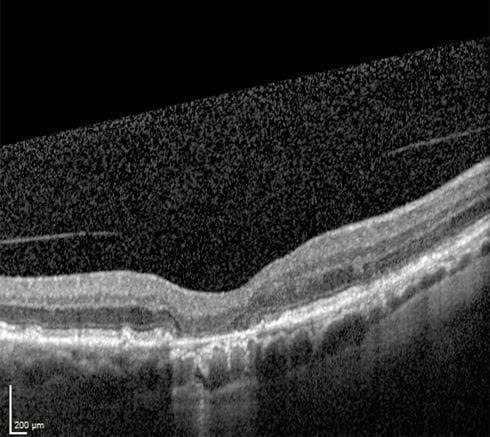

Hình ảnh OCT đáy mắt bình thường

Hình ảnh OCT đáy mắt AMD thể khô

Hình ảnh OCT đáy mắt AMD thể ướt